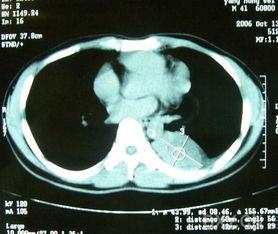

肿瘤照片,揭示癌症的视觉秘密